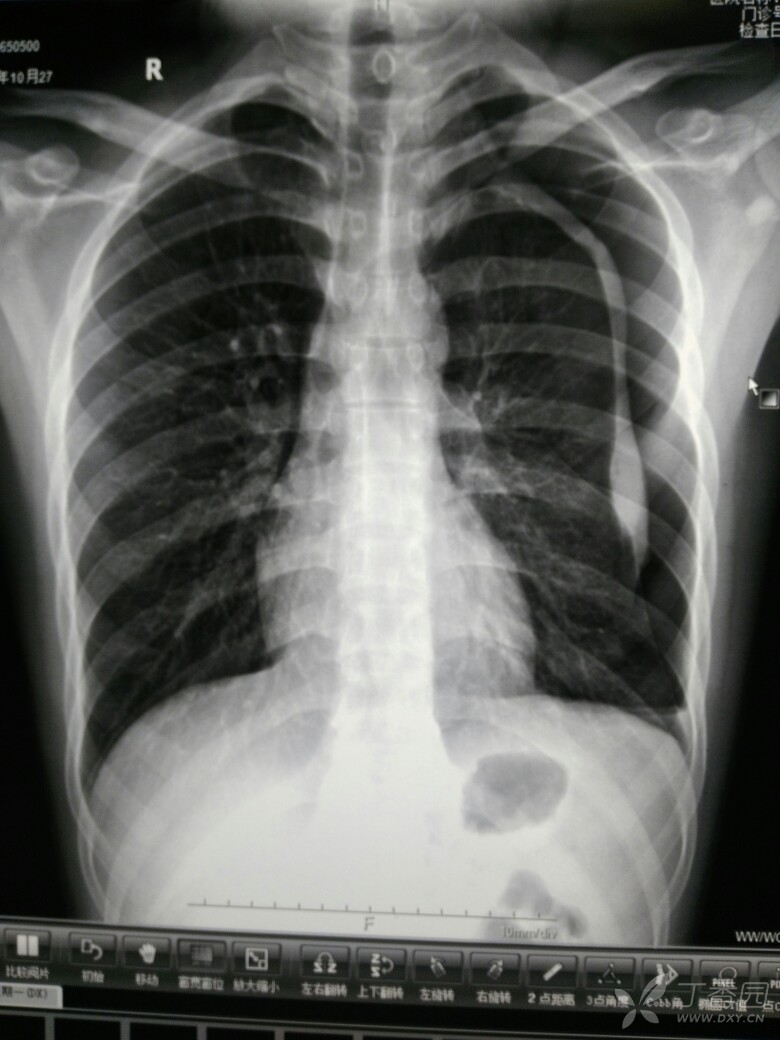

气胸x线x光

气胸x线x光,

第一次见!肺组织被压缩约30%的青年气胸

这样是气胸吗?

【影像读片】典型病例 反复气胸

气胸x线表现图片